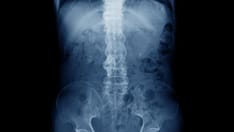

Initially, the organism may spread via lymphatic drainage of infected macrophages from the initial terminal bronchiole lesion, as demonstrated by sequential involvement of the hilar nodes, followed by the paratracheal and then supraclavicular nodes, and finally reaching the common lymphatic duct.

From the thoracic duct, spread of the infection becomes hematogenous. Certain host factors, clinical findings, and laboratory findings suggest dissemination including advanced age, immunocompromised state, late stages of pregnancy, and ethnic or racial factors (see Epidemiology).